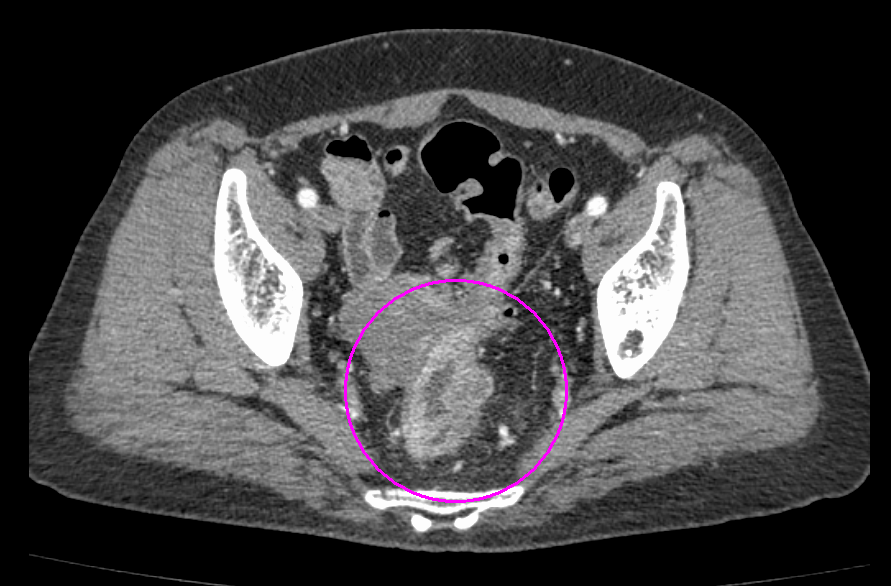

CT検査画像

大腸がんに対してTNT療法を行った例

治療前

治療後